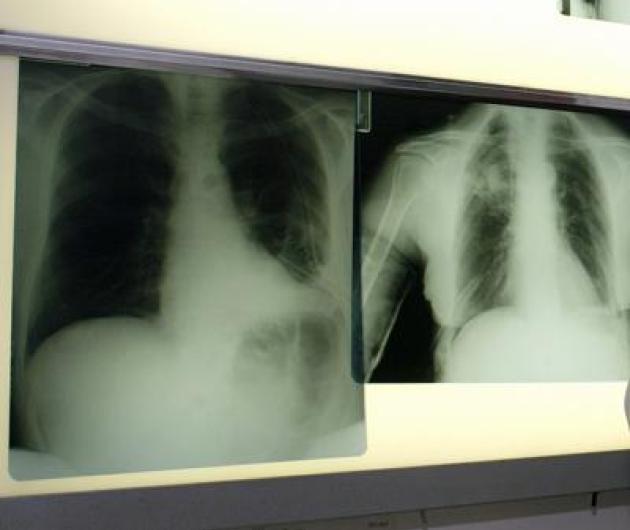

Roma, 7 ott. (Adnkronos Salute) - Ogni anno circa 290mila casi di infezione respiratoria acuta negli adulti e 1.800 decessi. Sono i numeri registrati solo in Italia per il virus respiratorio sinciziale (Vrs o Rsv nella sigla inglese), che si presenta con sintomi simil-influenzali, ma può determinare complicanze respiratorie significative nei soggetti fragili come over 60, persone immunocompromesse e neonati. Un fenomeno sottovalutato e sottostimato, specialmente nella popolazione adulta e anziana: spesso, infatti, la malattia da Rsv non viene diagnosticata correttamente. La protezione dei soggetti fragili resta la priorità: in Italia si registrano infatti oltre 50mila ricoveri all'anno. Nel dettaglio si calcano circa 25mila ospedalizzazioni di bambini sotto i 5 anni di età legate alle complicanze come bronchiolite e polmoniti, e circa 26mila negli over 60. Sul fronte della prevenzione, sono oggi disponibili strumenti sicuri ed efficaci come la vaccinazione e l'immunoprofilassi; nonostante queste opportunità, però, l'Rsv non è ancora incluso nel Piano nazionale di prevenzione vaccinale (Pnpv).

Il virus respiratorio sinciziale colpisce in modo diverso nelle differenti fasce d'età. L'Rsv "è un virus ubiquitario che colpisce praticamente tutti i bambini entro i 2 anni di vita, con possibili reinfezioni nel corso della prima infanzia e financo in età adulta - illustra Paolo Manzoni, professore associato di Pediatria e neonatologia, università di Torino – Se nei soggetti oltre i 2 anni di età il virus causa spesso sintomi simil-influenzali, colpendo per lo più le vie aeree superiori, al contrario una percentuale importante di pazienti con età meno di 2 anni presenta coinvolgimento delle basse vie aeree che può sfociare, nello specifico, nel quadro clinico classico conosciuto come bronchiolite e nelle sue complicanze sia immediate, sia a lungo termine". Oltre ai neonati prematuri e di età inferiore ai 6 mesi, le popolazioni a rischio di sviluppare una patologia respiratoria grave a seguito di Rsv sono le persone over 60 e quelle immunocompromesse o con patologie preesistenti come il diabete, le malattie cardiache e polmonari, nelle quali il virus può scendere alle vie respiratorie inferiori causando principalmente polmonite.